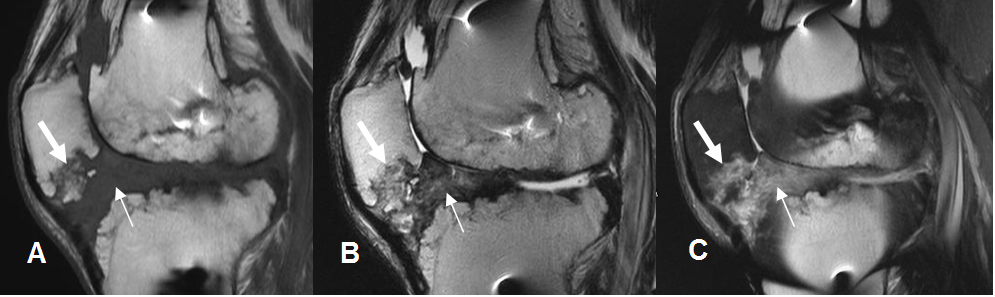

Fig 146 A. Artrofibrosis del injerto.

A: RM sagital en T1, B: ArtroRM sagital en STIR y C: ArtroRM axial en STIR. Presencia de imagen con señal de tejido blando, por delante del injerto, que corresponde a fibrosis.

Fig 146 B. Artrofibrosis del injerto.

A: RM sagital en T1, B: RM sagital en T2 y C: RM sagital en STIR. Abundante tejido de granulación hipointenso en T1 e hiperintenso en T2 y STIR, localizado entre la plastia del LCA (no vista) y la grasa de Hoffa, por artrofibrosis. Existe erosión en el polo inferior de la patela. (Flechas gruesas).